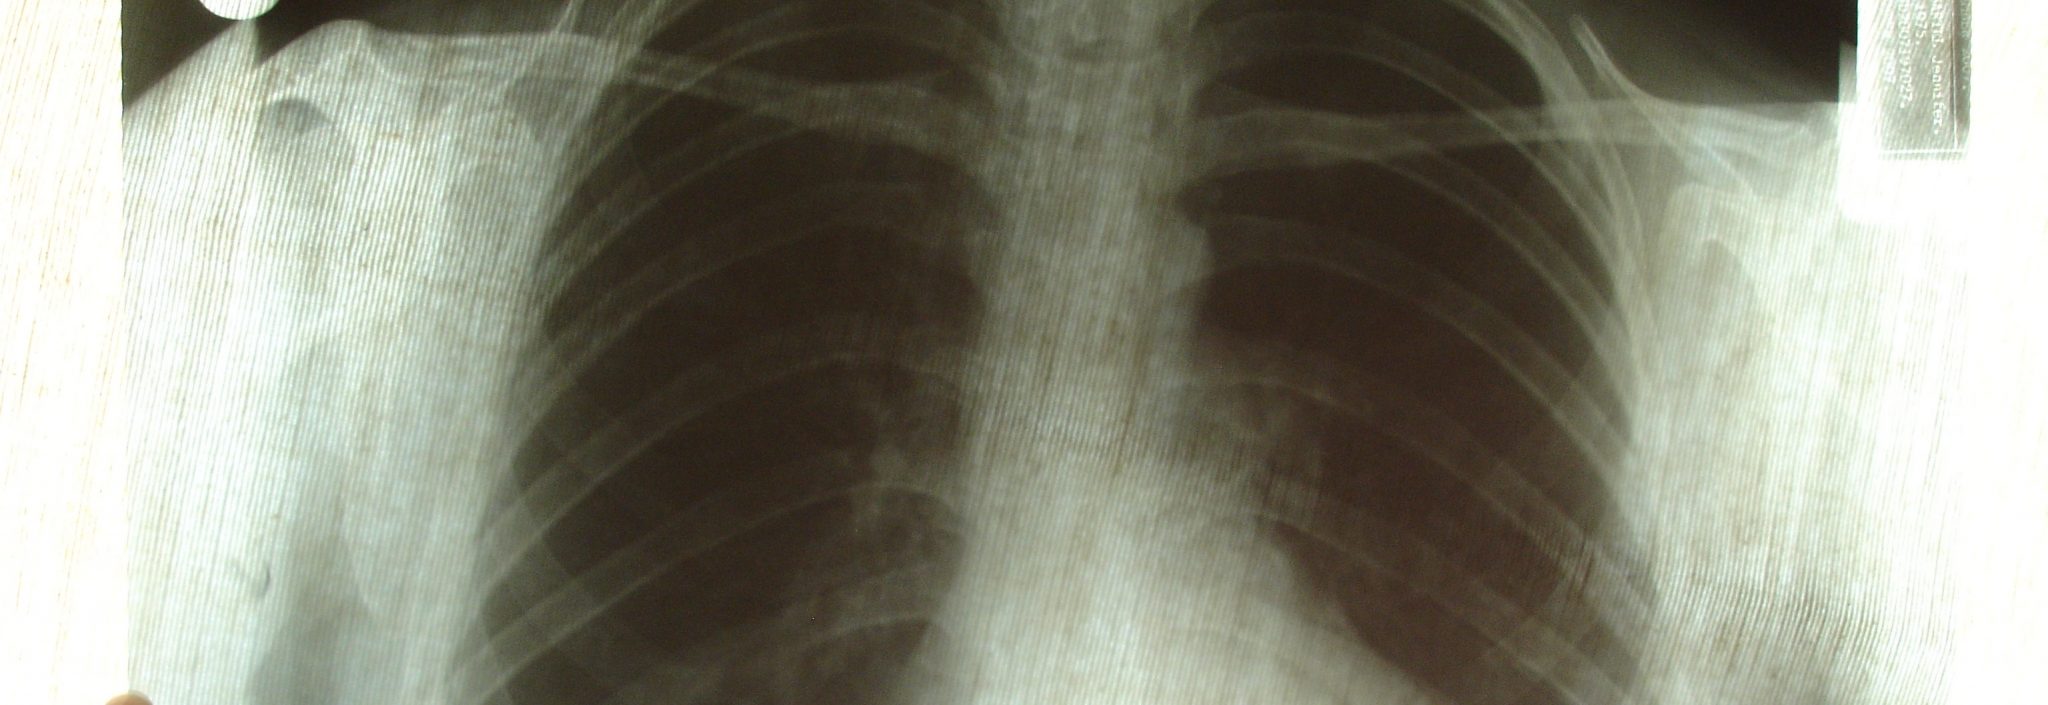

The medical sector is one of the most vibrant areas for additive manufacturing at the moment, with the technology establishing itself as an invaluable tool, both for education and on the hospital floor. Perhaps the most exciting time during any period of intensive innovation is when a relatively untested technology or technique is successfully put into practice. This might be to complete an ambitious project that showcases the concept’s possibilities, to make a tangible difference in someone’s life, or (best of all) both. The latter was definitely the case in July of this year, when surgeons at China’s Shanghai Changzheng Hospital employed a 3D printer to create titanium alloy bone implants for a cancer patient.The patient was suffering from a rare type of bone tumour in her spine -- one that is notoriously difficult to treat. The tumour had affected six separate bones in her spine, which would all need to be removed to prevent the cancer from returning later. Suffice to say, this was an extremely challenging operation, which ran the risk of leaving the patient paralysed or dead if anything went wrong. For medical implants of this nature, every element must be crafted with the absolute highest degree of precision. To craft the patient’s tailor-made bone implants, the team utilised a 3D model of the affected vertebrae, which would form the basis of the implants. Over the course of three weeks, the team designed the new bones in this virtual environment, then delivered them using a sophisticated metal 3D printer, to ensure the implants’ dimensions were captured with perfect accuracy. Crucially, the implants were designed in such a way that they eventually integrate with the patient’s natural bone material and mimic its behaviour, thanks to their microporous structure.We are pleased to report that after an intensive 13 hours, the operation was successful, and the patient is now recovering slowly. As new materials are developed for medical 3D printing and the technology evolves to fulfil the sector’s stringent regulatory requirements, we expect success stories like this to become increasingly common, as more hospitals are inspired to explore 3D printing technology.